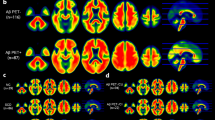

Figure 2 shows the results of the correlation analysis between MDS-OAβ level and cerebral AB deposition level (SUVR). Global SUVR (r = 0.323, p < 0.001) and regional SUVR of the PCC/PC (r = 0.344, p < 0.001), striatum (r = 0.253, p < 0.01), frontal lobe (r = 0.291, p < 0.001), parietal lobe (r = 0.247, p < 0.01), and lateral temporal lobe (r = 0.252, p < 0.01) showed a positive correlation with MDS-OAβ (Fig. 2A ~ F). Since the group analysis showed that MDS-OAβ was lower in the AD dementia group than in the A-PET-positive MCI group, we conducted an additional correlation analysis after excluding patients with AD dementia. The positive association between MDS-OAβ and SUVR persisted with a higher correlation coefficient: Global SUVR (r = 0.367, P < 0.001) and regional SUVR of PCC/PC (r = 0.417, p < 0.001), striatum (r = 0.353, p = 0.002), frontal lobe (r = 0.360, P < 0.001), parietal lobe (r = 0.248, p = 0.008), and lateral temporal lobe (r = 0.340, p = 0.001) (Fig. 3).